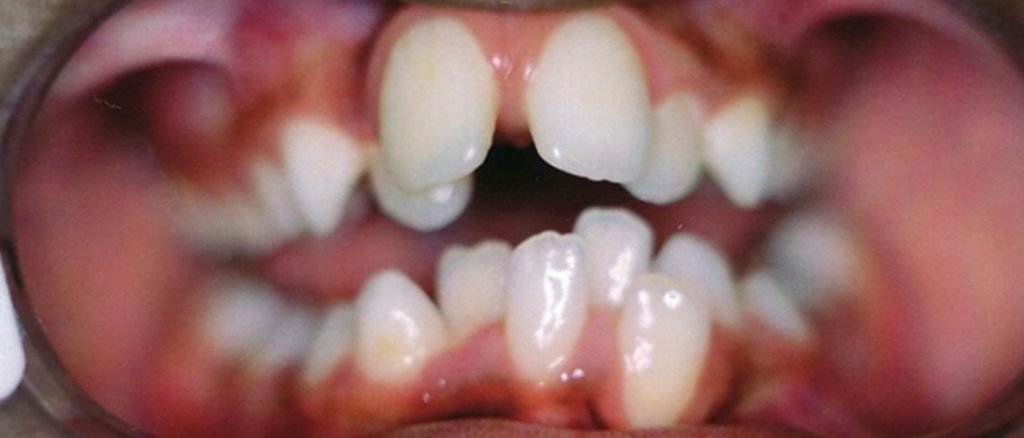

Kao što se vidi, ovaj šestogodišnji dječak imao je zbijene zube u trenutku kada su njegovi roditelji odlučili reagovati zbog ortodontskih briga. Klasičan savjet bi bio da se sačeka da izrastu svi stalni zubi i tek tada razmotri fiksna terapija. Međutim, roditelji nisu željeli čekati, te je nakon 12 mjeseci Myobrace® terapije zbijenost zuba uspješno korigovana.

PRIJE

POSLIJE